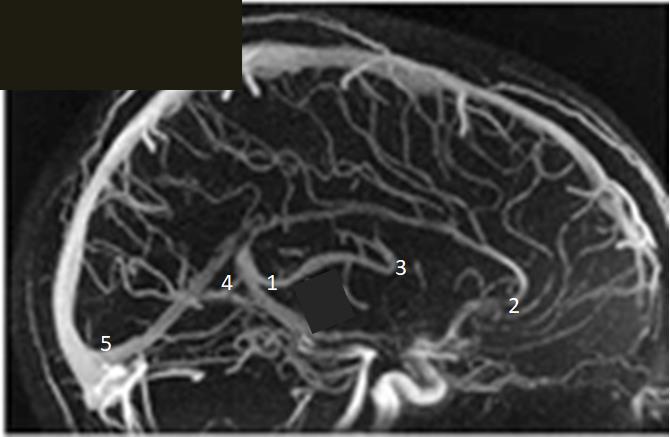

Rycina przedstawia fazę żylną angiografii mózgu. Która z cyfr odpowiada miejscu lokalizacji otworu międzykomorowego Monro: